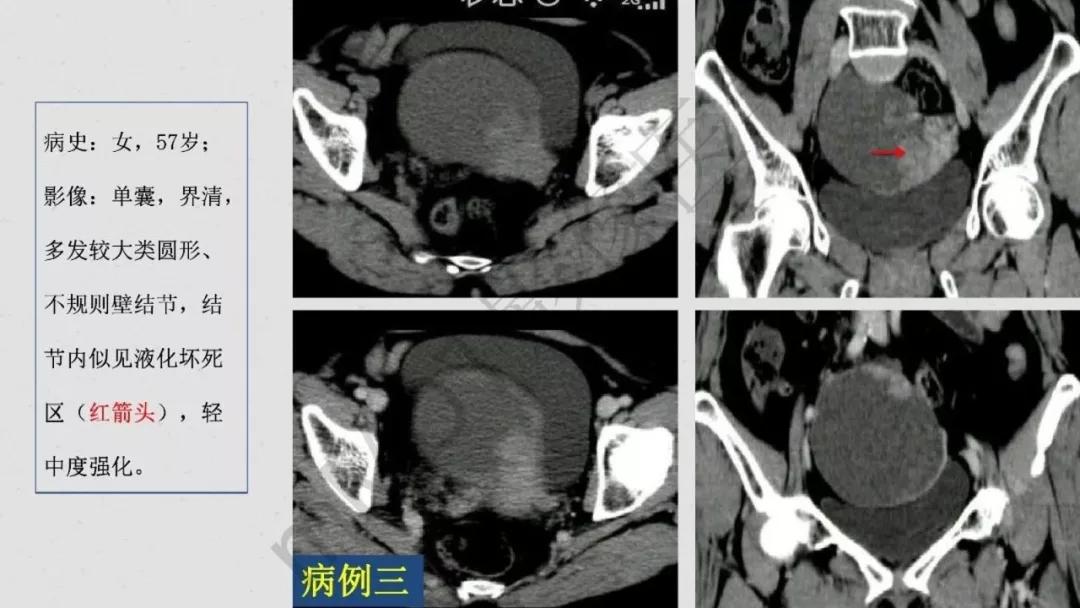

上皮性肿瘤:最常见,恶性多(卵巢癌),良性少。好发于50Y以上,发现时多为中晚期。多呈囊性或以囊性为主的囊实性肿块,完全实性者少见。形态多数不规则,边界模糊,囊壁及房间隔常不规则增厚,菜花样肿物或壁结节,囊实性区域分界不清,实性肿瘤常有不规则低密度或坏死区,可有边界模糊沙粒状或块状钙化,中-高度强化。良性者边界清晰,囊壁薄光整,无壁结节,实性部分呈无或轻度强化。